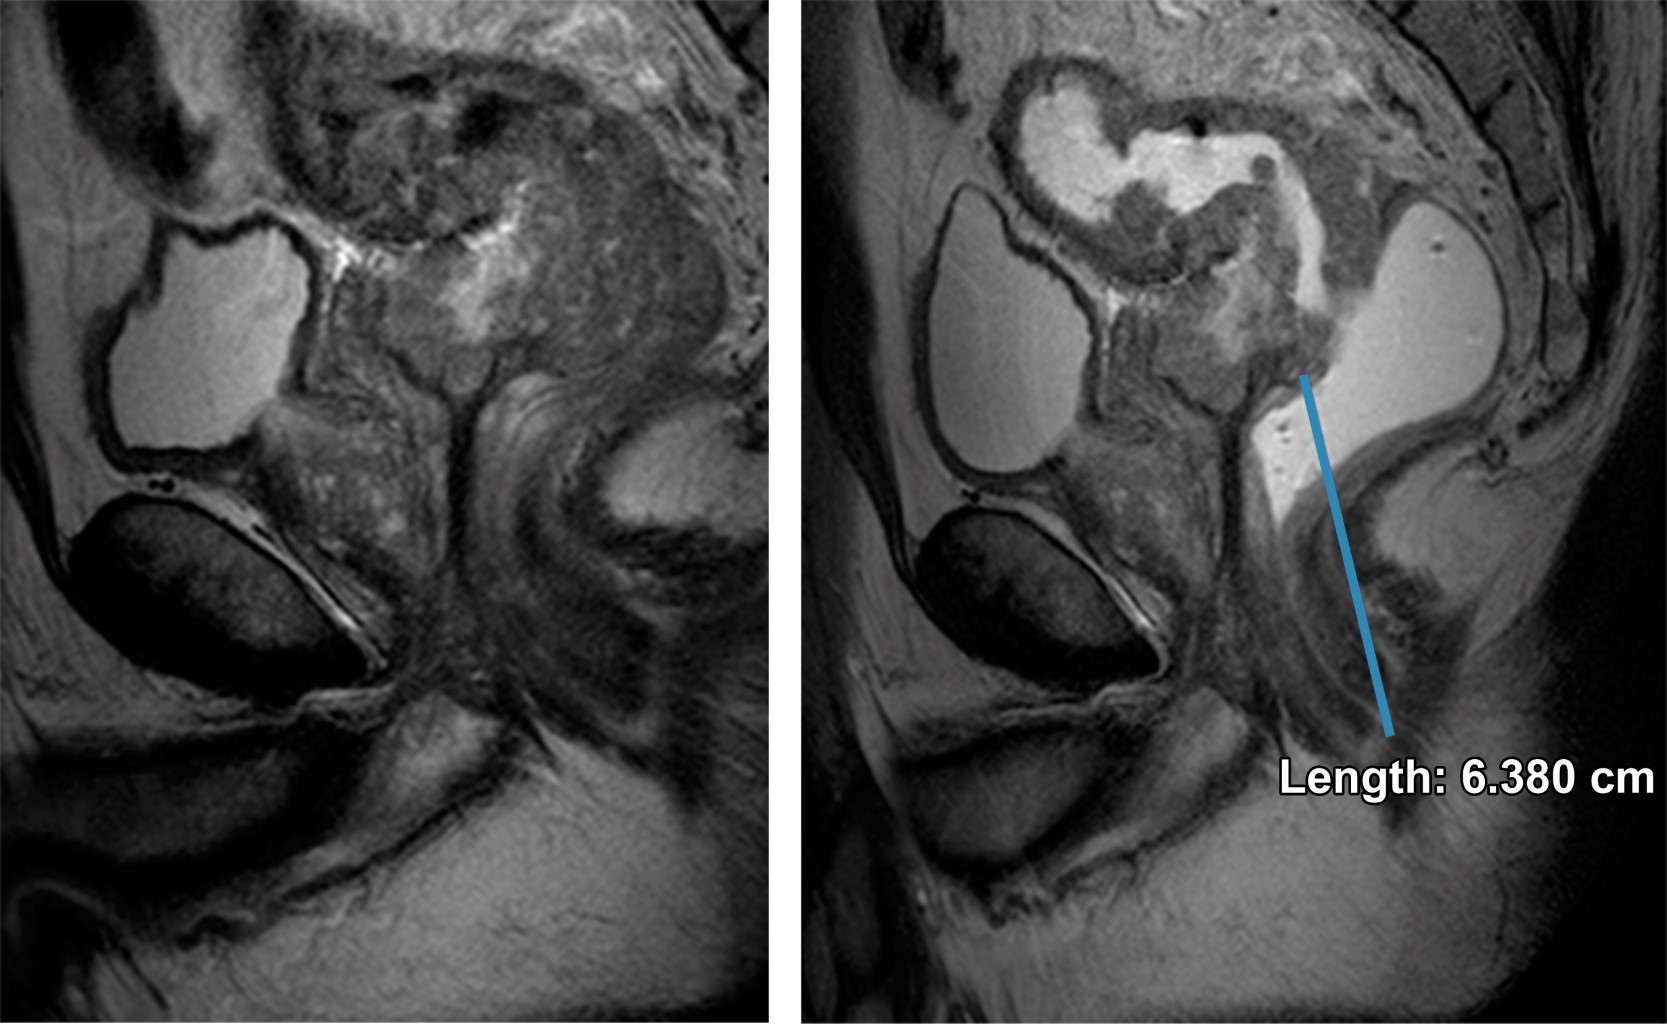

Paciente masculino de 64 años de edad, sin antecedentes personales de importancia, que hace aproximadamente seis meses presenta cambios en los hábitos intestinales con periodos de estreñimiento y diarrea que se acompañan de heces acintadas y rectorragia, por lo que acude a médico tratante quien envía resonancia magnética para valoración de recto.

En el caso expuesto se realizó un protocolo de resonancia magnética con secuencias de T2, difusión, ADC y administración de gadolinio en planos axial, sagital y coronal con y sin la aplicación de gel endorrectal, obervándose los hallazgos descritos en las Figuras 1, 2 y 3; características que se valoran con exactitud y gran detalle anatómico, requerimientos indispensables para una correcta estadificación.

Se catalogó esta lesión como T4aN1b.

Figura 2

Figura 3